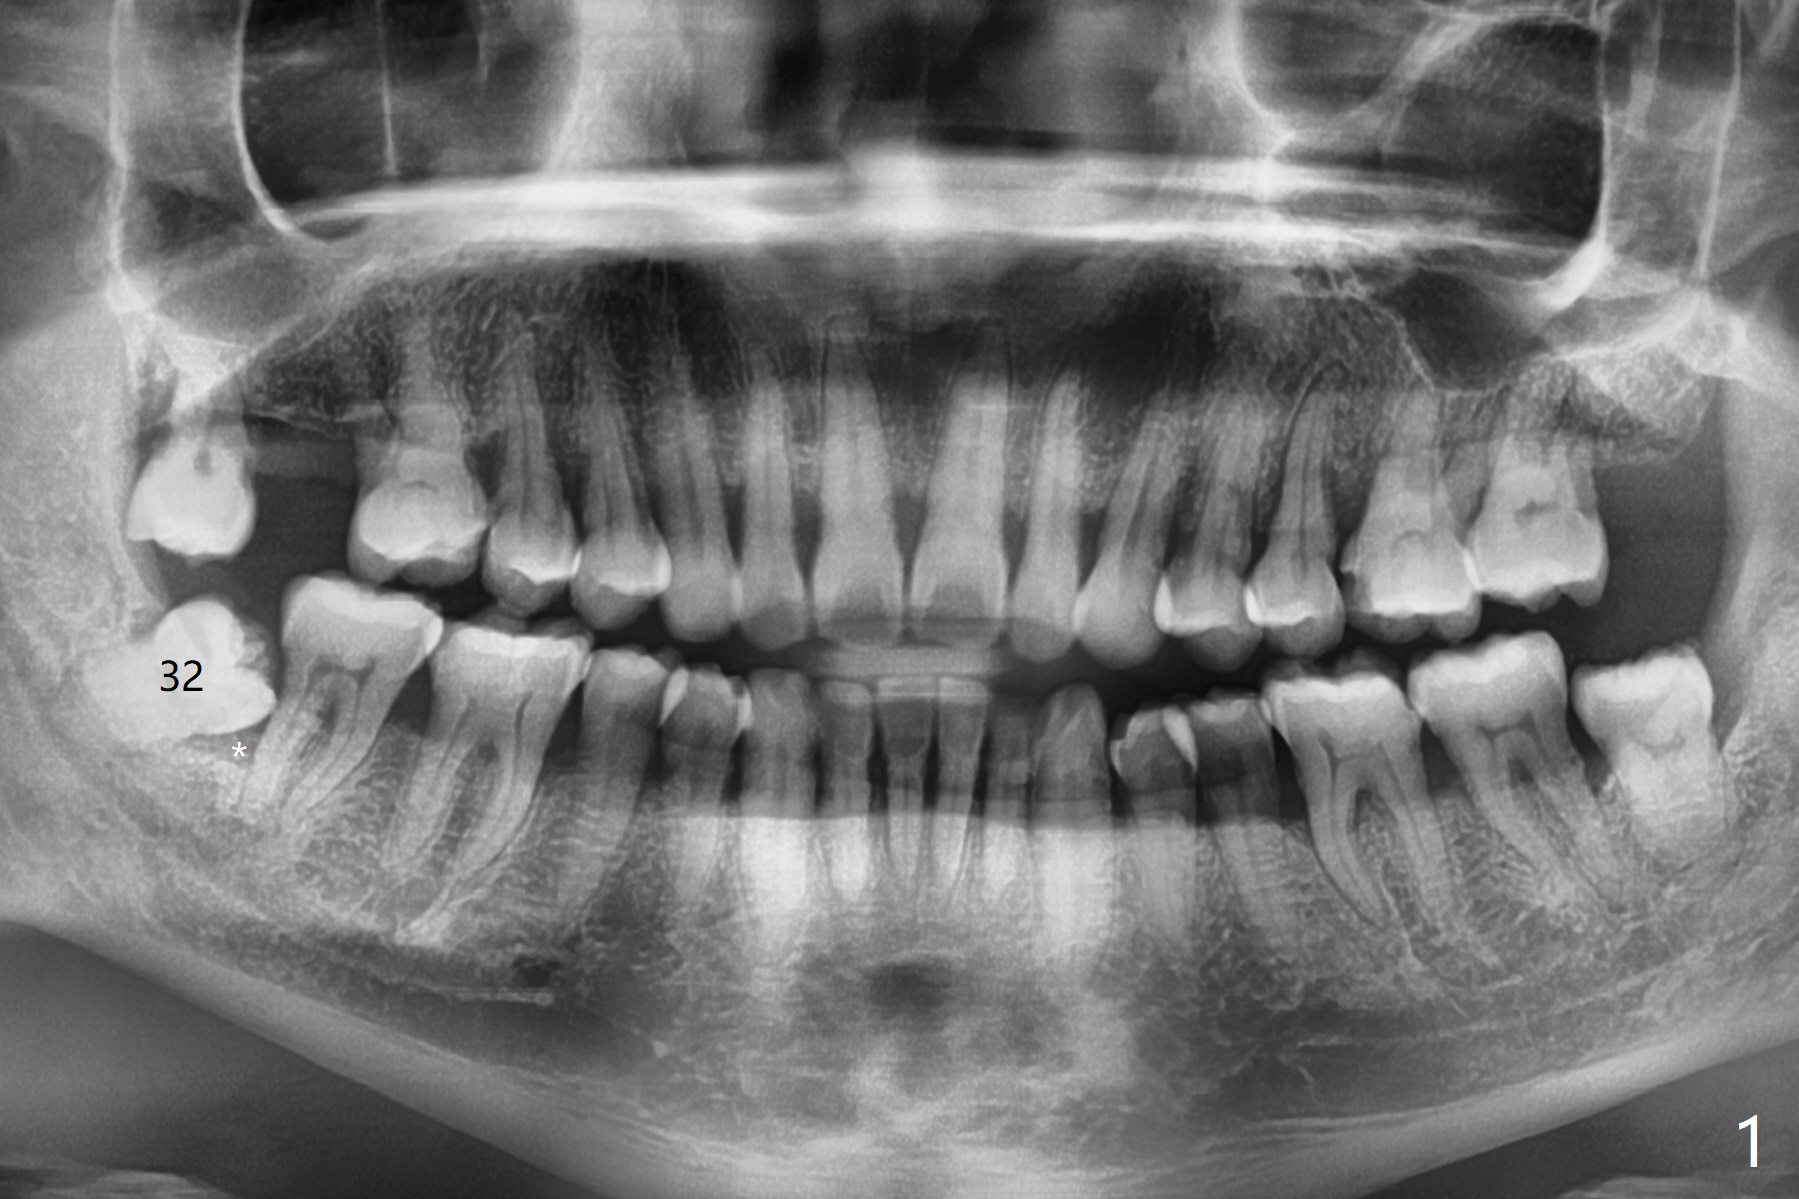

47岁男,牙周炎,吸烟(一天一包),忍受右下智齿(32)疼痛多天后来诊所要求拔除(中国老百姓认为疼痛期间不能拔牙, 图一),第二磨牙远中骨质吸收严重(*),植骨是必须的。为了顺利成骨(与方炳忠医生根管治疗之后调整咬合一致),拔除智齿前,对第二磨牙近中颊侧咬合面进行降低(图二:箭头)。为了止血和减少骨粉使用量,牙槽窝远中放置胶原骨(Osteogen Plug,O),而第二磨牙远中放置粘性骨粉(sticky bone (allograft),S),后者也是必须的,因为在炎症期间,拔除智齿,出血严重,一般骨粉容易被血冲走。下次植骨前牙槽窝必须放置含肾上腺素纱布止血。最后牙槽窝表面放置两块PRF膜(P),严密缝合。术后服用Amoxicillin, Medrol Dose Pak and Tylenol III。